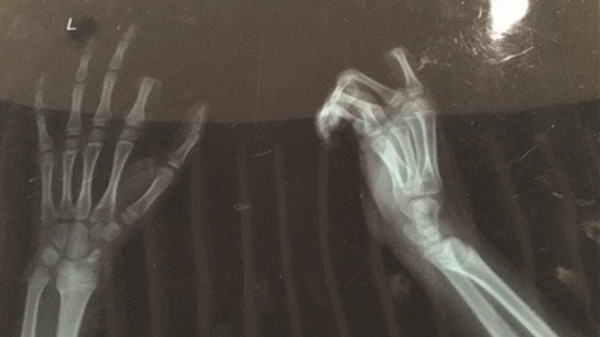

Ảnh chụp X-quang bàn tay bị đứt ngón của Peng.

Ngày 5/3, cậu bé tên Peng được đưa đến bệnh viện ở thành phố Tô Châu (Trung Quốc) trong tình trạng ngón tay trỏ bị đứt lìa, trang mạng Huanqiu thuộc tờ People's Daily cho biết.

Cha mẹ Peng lập tức đưa cậu bé vào bệnh viện dù chưa kịp hoàn hồn trước hành vi cực đoan của con trai. May mắn, do được đưa đi cấp cứu kịp thời, các bác sĩ nối lại ngón tay bị đứt sau ba giờ phẫu thuật.

Bác sĩ Zhou Rong, thành viên kíp mổ, cho hay: “Hiện tại ngón tay đã được kết nối một cách tạm thời. Tuy nhiên, để đảm bảo chắc chắn, chúng tôi cần theo dõi thêm một thời gian”.

Theo lời khuyên của bác sĩ, Peng phải cẩn thận khi cử động ngón tay vì có thể xảy ra tình trạng nghẽn mạch dẫn đến nguy cơ hoại tử hoàn toàn.